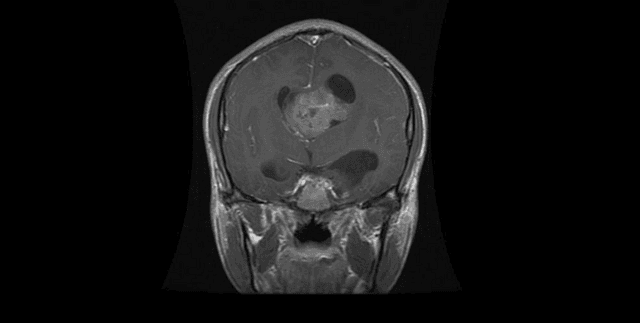

Brain magnetic resonance imaging (MRI) data curated specifically for image classification tasks in health and cancer research. The data consists of MRI images categorised into four distinct groups: Glioma, meningioma, pituitary, and 'no tumor' cases. The primary function of this collection is to facilitate the training and evaluation of machine learning models aimed at identifying different brain tumour types. The data is pre-divided into Training and Testing subsets to support immediate classification work.

The data covers MRI images of brains focusing on four distinct diagnostic categories: Glioma, meningioma, pituitary tumors, and healthy (no tumor) subjects. The expected update frequency for this specific version of the dataset is stated as 'Never'. There is no explicit geographical, temporal, or demographic information provided within the scope of the sources.